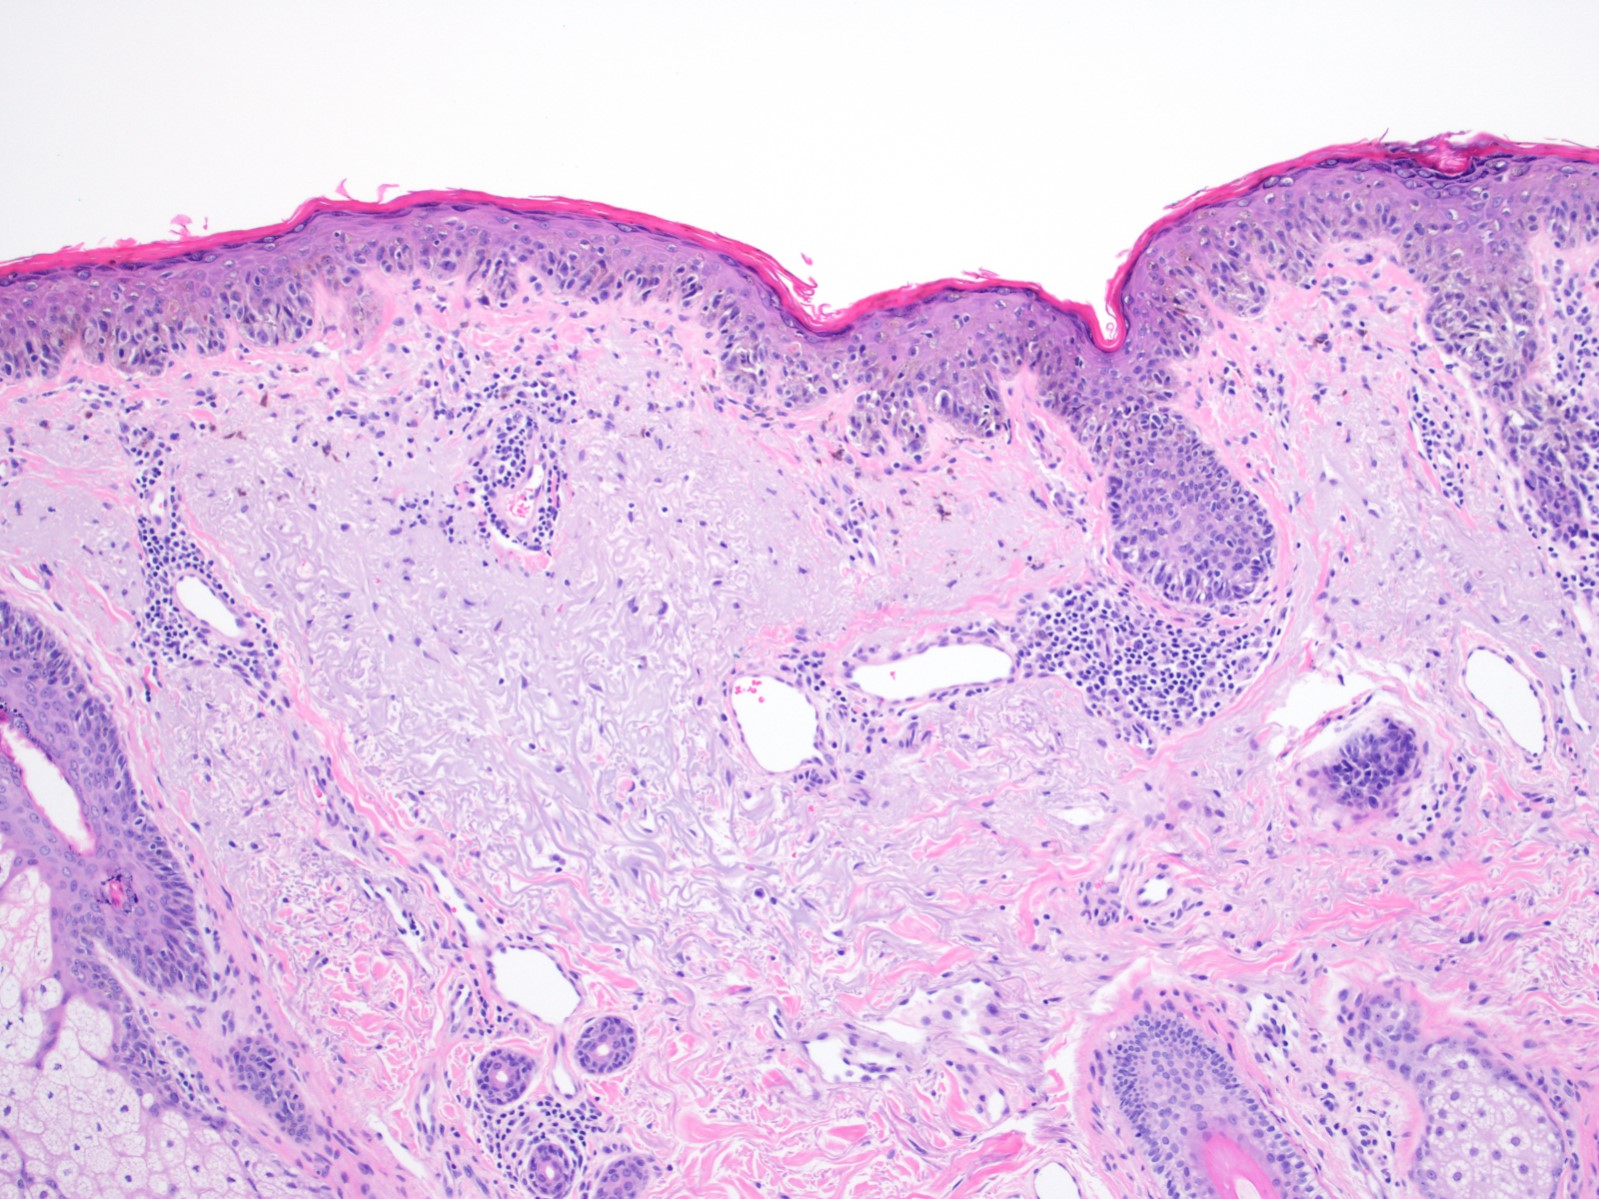

Microscopic (histologic) description

- Proliferation of intraepidermal (single and nested) melanocytes overlying solar elastosis

- Melanocytes demonstrate crowded growth along the basal epidermis

- Associated epidermal alterations, including loss (effacement) of epidermal rete and associated irregular epidermal hyperplasia

- Pagetoid scatter (melanocytes above the basal layer)

- Involvement of adnexal epithelium

- Melanocytic cytology is variable, ranging from small cells with dark nuclei and scant cytoplasm to epithelioid pigmented melanocytes, to spindled melanocytes

- Invasive component, if present, consists of single or nested melanocytes in the dermis with similar cytologic features to those in the in situ component (Cancer Res 1969;29:705, Am J Pathol 1969;55:39)

Microscopic (histologic) images

Contributed by Joseph Gillam, M.D., Jennifer Crimmins, M.D. and Mark Mochel, M.D.